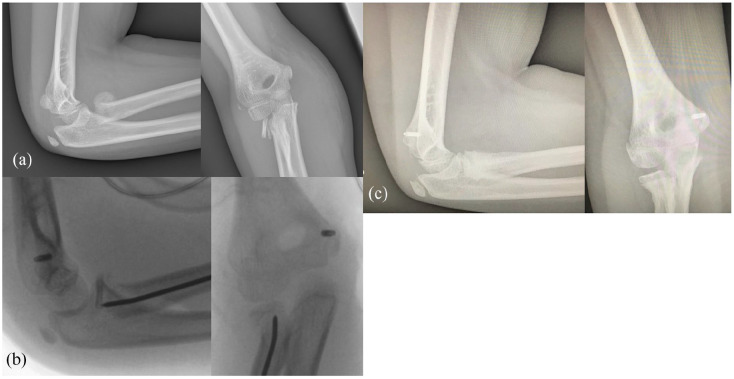

Background: The aim of this study was to describe the epidemiology, physiopathology, and outcomes of elbow "unhappy triad" trauma in children, combining a posterior dislocation, a proximal radius fracture, and a third lesion (i.e. bony or capsuloligamentous injury).

Methods: A retrospective bicentric study was conducted between 1999 and 2020. All skeletally immature children who presented to the emergency department and underwent surgery for a proximal radius injury were selected. Among this selection, only patients with two associated ipsilateral elbow injuries (i.e. posterior elbow dislocation and a bony and/or capsuloligamentous injury) were included. Active elbow ranges of motion, Mayo Elbow Performance Score and Quick-Disabilities Of The Arm, Shoulder And Hand scores and standard radiographs were recorded at last follow-up.

Results: Twenty-one patients met the inclusion criteria (mean age at surgery = 11.4 years) among 737 selected. The "unhappy triad" diagnosis was made preoperatively in nine cases (bone lesion only), intraoperatively in nine cases, and postoperatively in one case. The third lesions were surgically treated when the lesion was a bony fracture or if the elbow remains unstable between 60° and 90° of flexion (i.e. capsuloligamentous injury). Twenty patients were reviewed (mean follow-up = 5.8 years). The complications and re-operations rates were of 10%.

Conclusion: The "unhappy" triad of the child's elbow is a rare injury, where the preoperative diagnosis is frequently missed and lead to 10% of complications and re-operations.